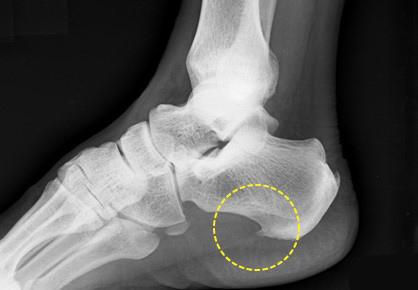

4. 족저근막염

족저근막염은 족저근막이라는 부위가 손상이 되면서 발현되는 질병입니다. 발바닥 안쪽에 있는 족저근막의 문제가 생기면 가장 먼저 발뒷꿈치가 찌릿찌릿한 느낌을 받게되며, 시간이 지나면서 종아리 통증을 동반하게 됩니다.

보통 일상생활을 할 때는 괜찮다가 휴식을 취할 때 큰 통증과 함께 찾아오는 특징이 있으며, 심해지면 일상생활에도 큰 문제를 가져다 줍니다. 족저근막염은 종아리 통증 전, 발뒷꿈치 통증이 있을 때 병원을 방문하는 게 좋습니다.